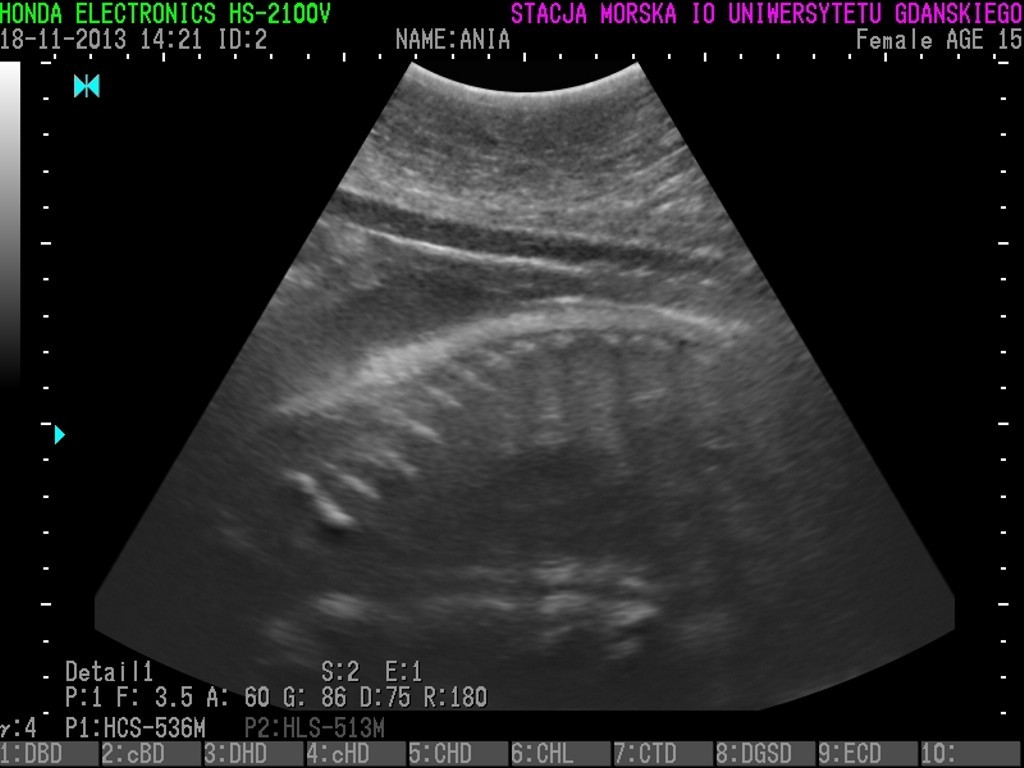

Unda Marina, Ewa i Ania urodzą? Badania 3 fok wskazały, że znajdują się w zaawansowanej ciąży i jeśli nie wydarzą się żadne nieprzewidziane okoliczności, na początku marca możemy spodziewać się trzech młodych osobników.

Dzięki specjalistycznemu sprzętowi, zakupionemu przy wsparciu WWF wiadomo, że focza ciąża przebiega obecnie bez większych problemów. Wkrótce będziemy mogli poznać również płeć fok.